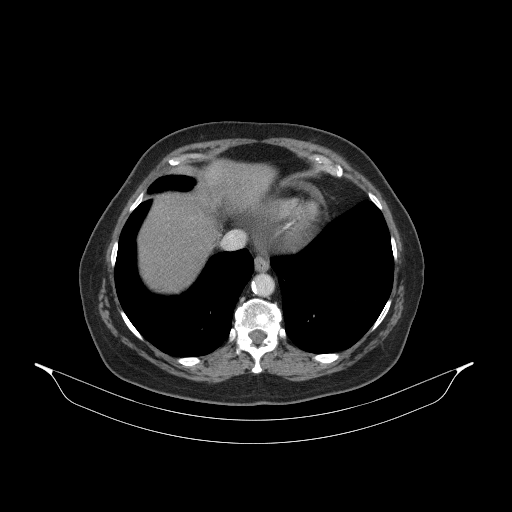

Original NATIVE CT scan (input)

Full window (WL 1023.5, WW 4095 β†’ Low βˆ’1024, High +3071)